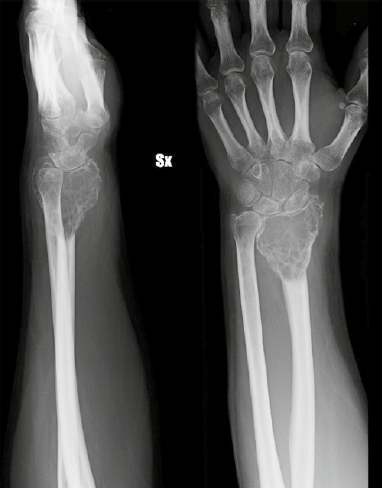

Overall, the choice between arthrodesis and joint-preserving procedures should be individualized, balancing oncologic safety with functional expectations. Factors such as tumor grade, local bone involvement, patient age, occupational demands, and long-term priorities play a decisive role in guiding reconstruction strategy 6,9,14. This tailored approach ensures that surgical management not only secures tumor control, but also provides the most functional and durable outcome for each patient. In Figures 1-3 we present an example case of 28-year-old man with a distal radius GCT resected after denosumab medical treatment and reconstructed with an arthrodesis with microsurgical free fibula (Tab. IV, Figs. 1-3).

Figure 1.Male 28ys. GCT of the distal radius after denosumab medical treatment.